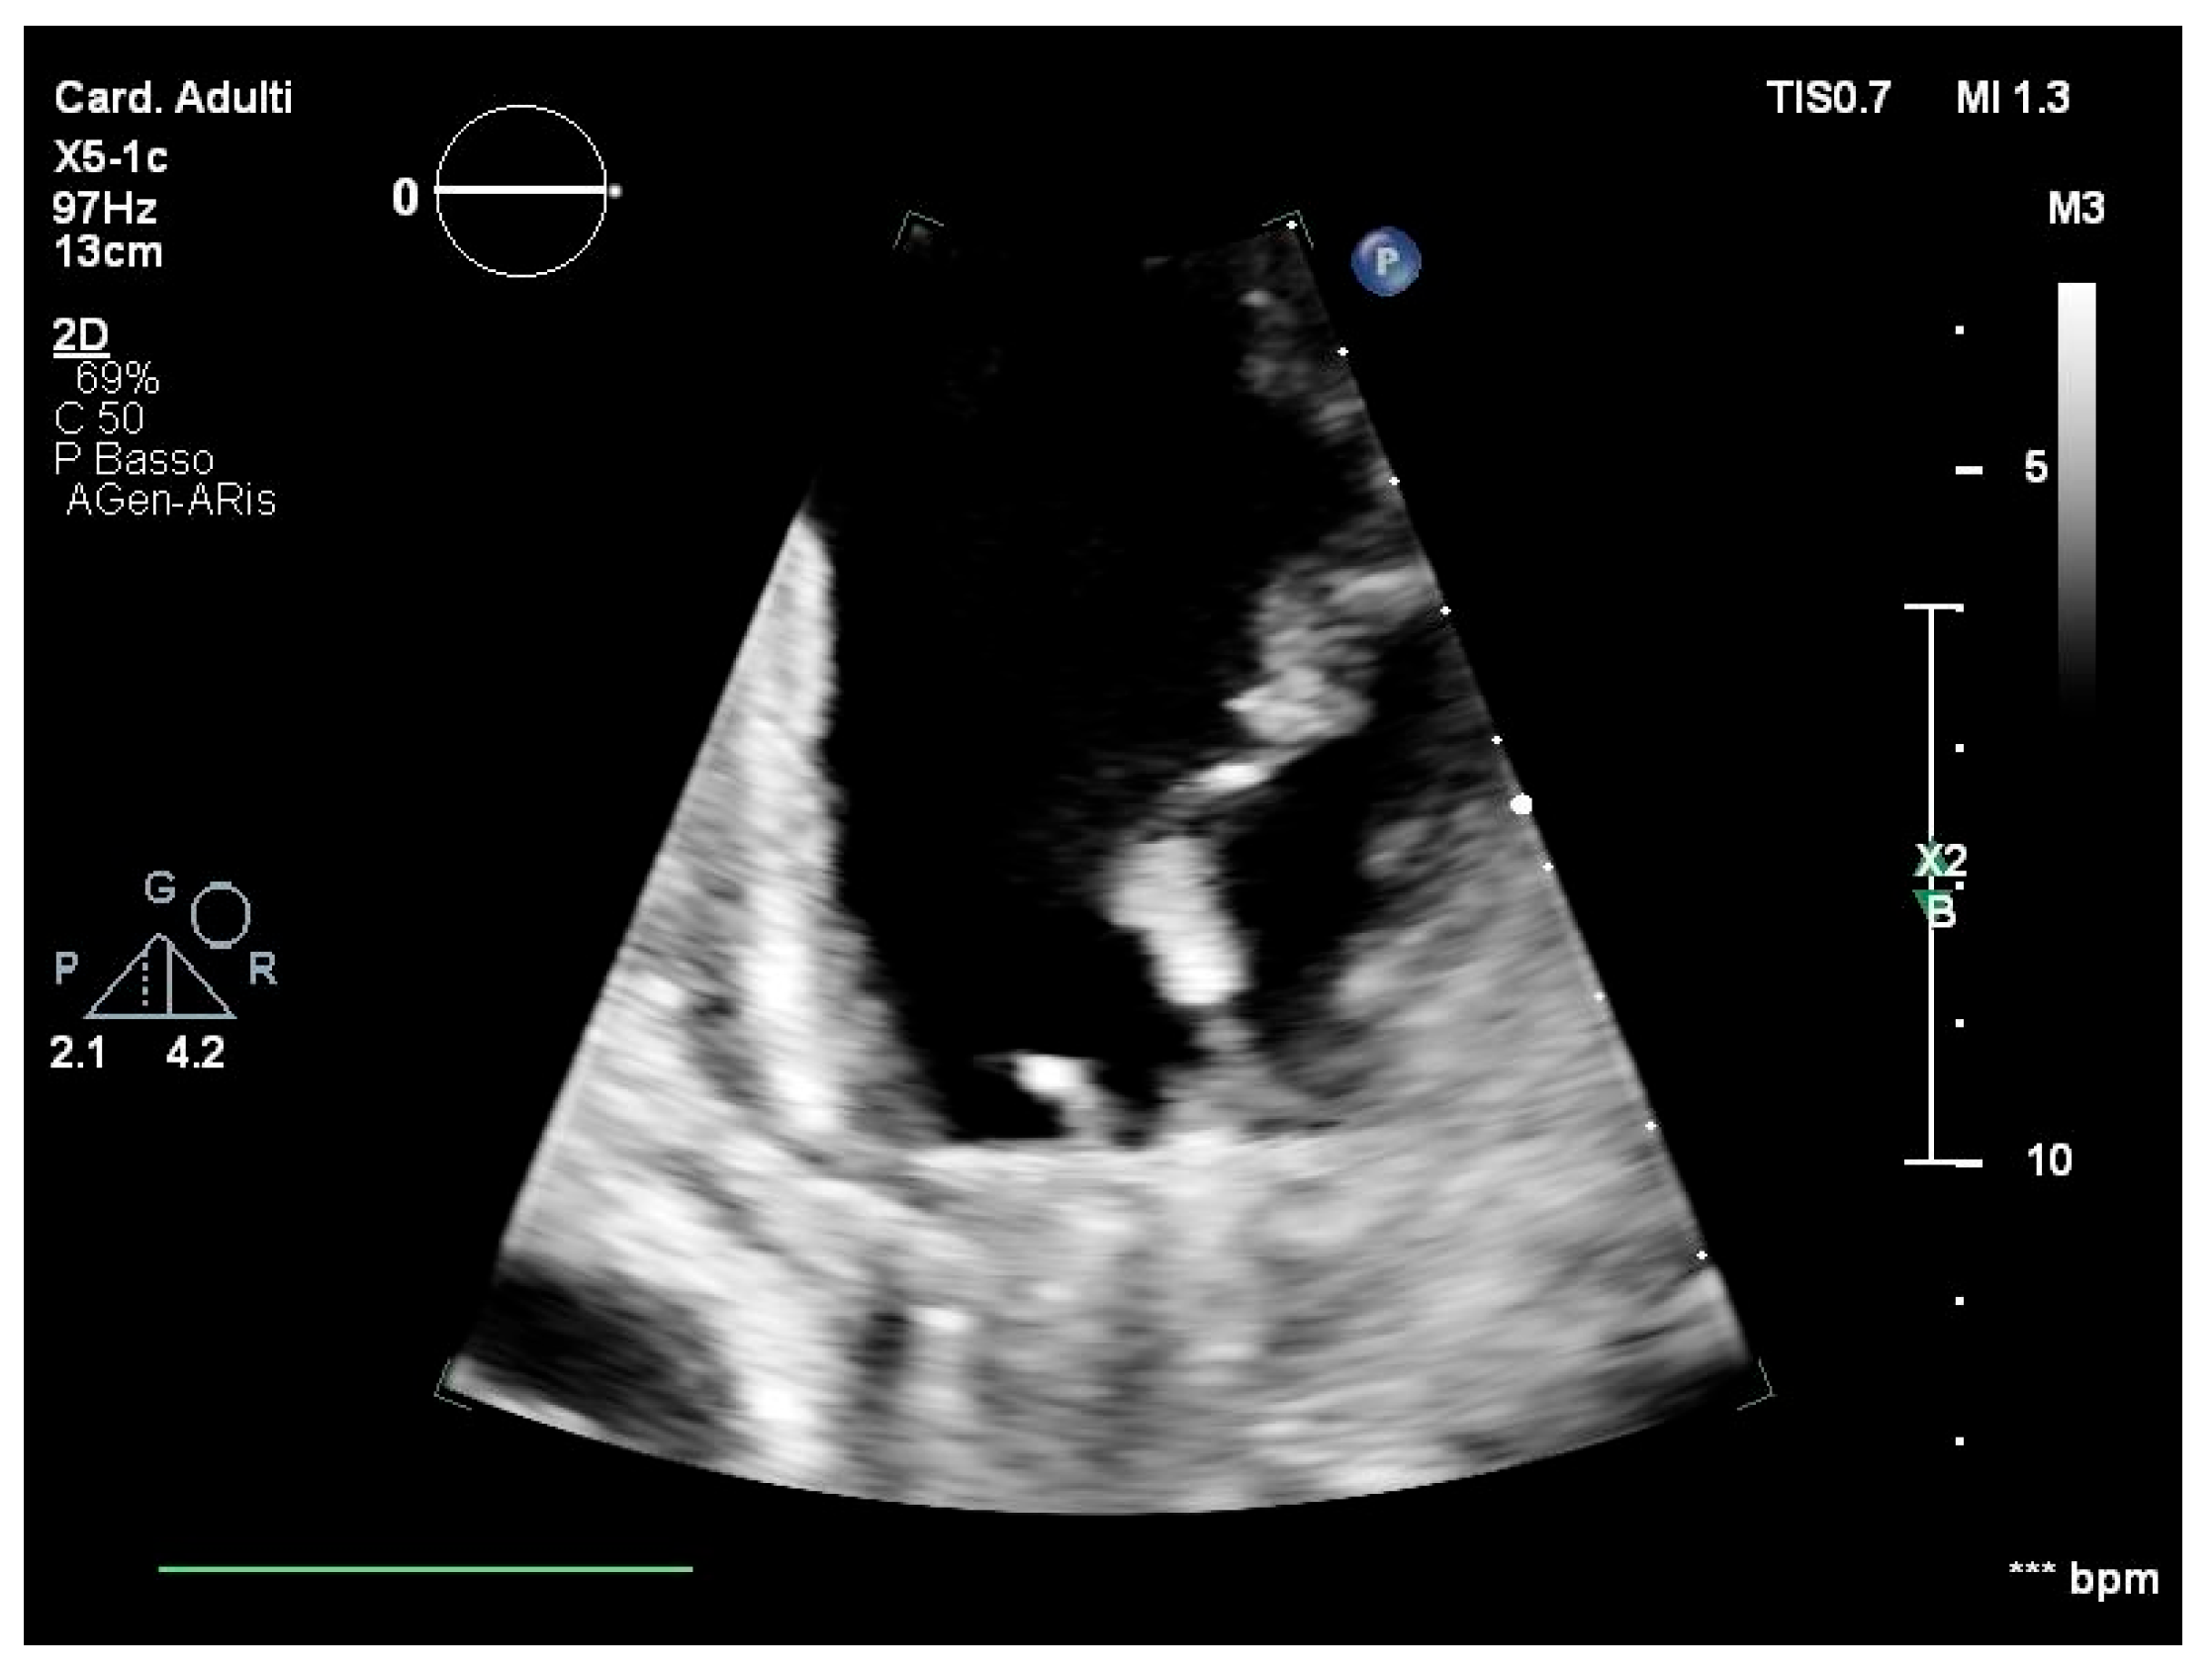

2. Case Report